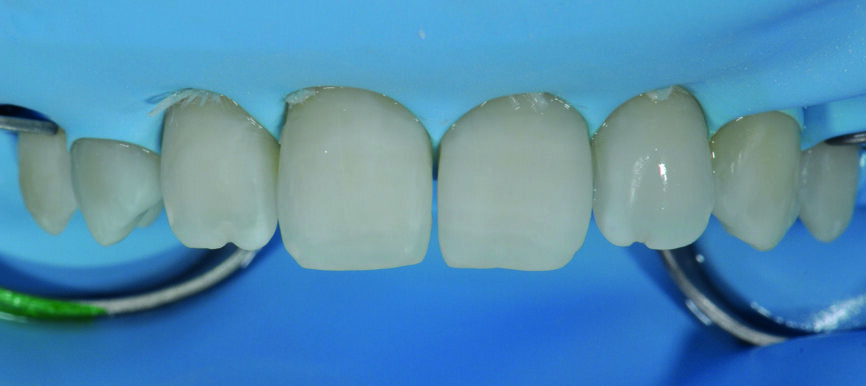

Fig. 5 : a) Après la mise en place de la digue en caoutchouc.

Fig 5b) : Les surfaces dentaires ont été légèrement sablées pour obtenir une performance adhésive optimale.

Fig 5 c) : La sélection des matrices et une mise en place adéquate sont importantes pour créer un profil d’émergence naturel.